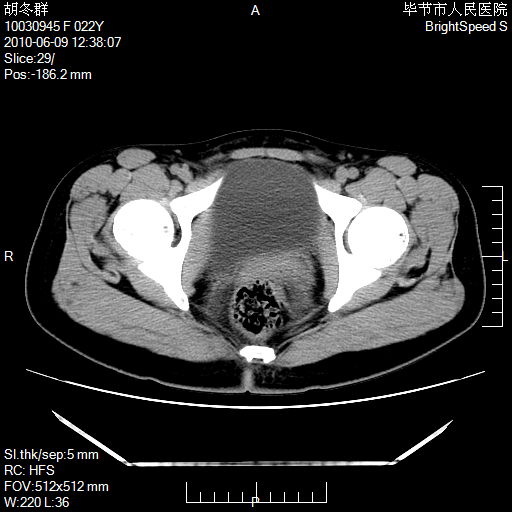

患者23岁,发现腹部包块3月。

盆腔内囊性占位;穿刺或者直接手术拿掉即可,不必紧张。

盆腔内囊性占位性病变;考虑左侧卵巢囊腺瘤。

有分隔、壁薄,支持考虑左侧卵巢囊腺瘤。

左侧卵巢浆液性囊腺瘤。

有分隔、壁薄,支持考虑左侧卵巢囊腺瘤。排尿后,膀胱缩小,由于重力作用,肿块下移就到了膀胱位置,很好理解。